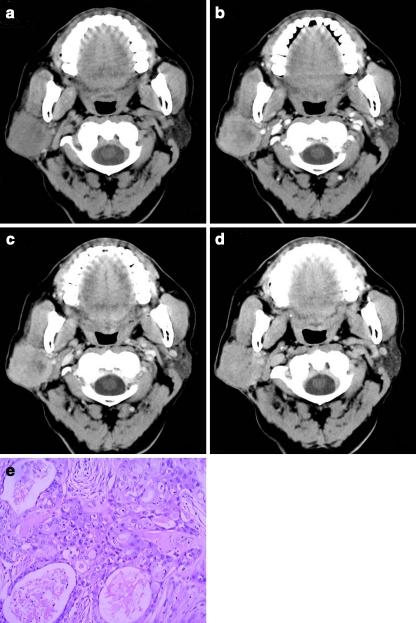

鉴别腮腺良恶性肿瘤:5 分钟延迟的低剂量多期 CT 方案。

Distinguishing benign from malignant parotid gland tumours: low-dose multi-phasic CT protocol with 5-minute delay.

To explore the percentage enhancement wash-out ratio (PEW) and relative PEW (RPEW) of low-dose multi-phasic computed tomography (CT) in distinguishing benign from malignant parotid gland tumours.

METHODS

This study was approved by the ethics committee, and informed patient consent was obtained. 51 patients with parotid tumours proven by histopathology received CT, including 18 with pleomorphic adenomas, 14 with Warthin's tumours and 19 with malignant tumours. Size and attenuation of parotid tumours were measured. Compared with 5-min attenuation, the 30-s and 90-s PEW (PEW(30,) PEW(90)) and RPEW (RPEW(30), RPEW(90)) were calculated.

RESULTS

There was a significant difference in PEW(30), RPEW(30), PEW(90) and RPEW(90) in the parotid neoplasms groups (P < 0.01), and statistical significance existed simultaneously in pleomorphic adenomas vs malignant tumours and Warthin's tumours vs malignant tumours according to SNK-q test. The optimal diagnosis results of malignancy with 100% specificity (32/32) was obtained by using a combination of the following criteria: -70% > PEW(30) < 36%, -30% > PEW(30) < 19%, PEW(90) > 12%, and the sensitivity (74%) for diagnosis of malignancy was yield.

CONCLUSIONS

Wash-out ratio may assist in differentiating the benign from malignant parotid gland tumours. Combining the percentage of enhanced wash-out ratios of CT protocols can yield diagnostic results for malignancy.